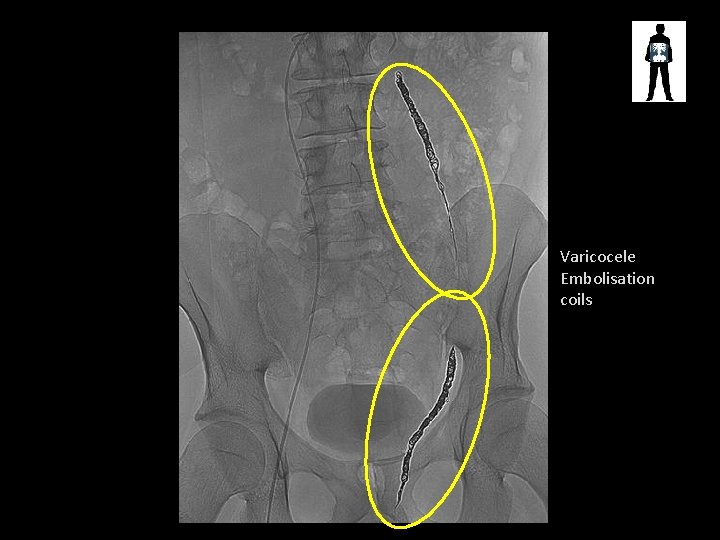

Small bowel pattern Surgical clips Artefacts? ? Embolisation coils SMALL BOWEL OBSTRUCTION

Varicocele Embolisation coils

Varicocele Embolisation Coils • Varicocele – enlarged scrotal vein – Causes pain, swelling, leads to infertility – Treated via embolization with coils or embolic fluid